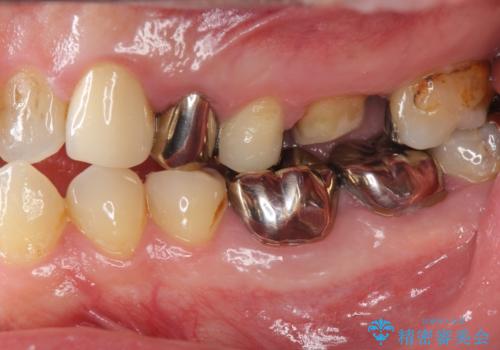

銀歯・虫歯・治療途中の歯を治していきたい